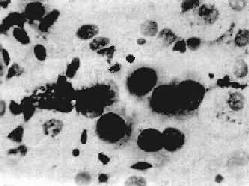

肺癌患者预后大多不良,早期发现、早期诊断和早期治疗至关重要。对于40岁以上的成人,特别有长期吸烟史并伴有咳嗽、痰中带血、气急、胸痛等症状者,或无痰干咳及与体位有关的刺激性呛咳的患者,必须提高警惕,及时进行X线、痰涂片细胞学(图9-35)和纤维支气管镜等检查,以及取活检组织作病理学检查,对肺癌的早期诊断具有重要价值。

图9-35 痰涂片中的肺腺癌细胞

癌细胞圆形,核大、浓染,染色质粗,核仁大而明显,胞浆少